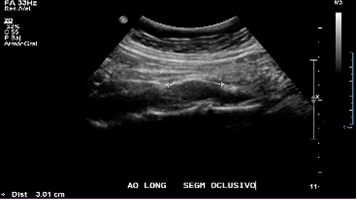

Se observa segmento oclusivo a nivel de la aorta abdominal (de 3 cm aprox.) previo a la bifurcación de las iliacas, con contenido ecogénico y ateromatosis cálcica asociada, sin flujo a este nivel.

Previo a la oclusión se observa curva pre oclusiva monofásica de baja velocidad.

Se observan curvas monofásicas de baja resistencia con pérdida de componente reverso diastólico y disminución de la velocidad sistólica en todo el árbol arterial de ambas extremidades inferiores. En la aorta abdominal distal, a 3 cm de la bifurcación, se observa un segmento oclusivo de la aorta con contenido ecogénico calcificado, sin flujo a este nivel. Previo a la oclusión se observa curva pre oclusiva monofásica de baja velocidad. Se observa flujo colateral paralelo a la oclusión que reconstituye el flujo en el origen de las arterias iliacas comunes, observándose flujos monofásicos hacia distal con reducción en aproximadamente un 60%